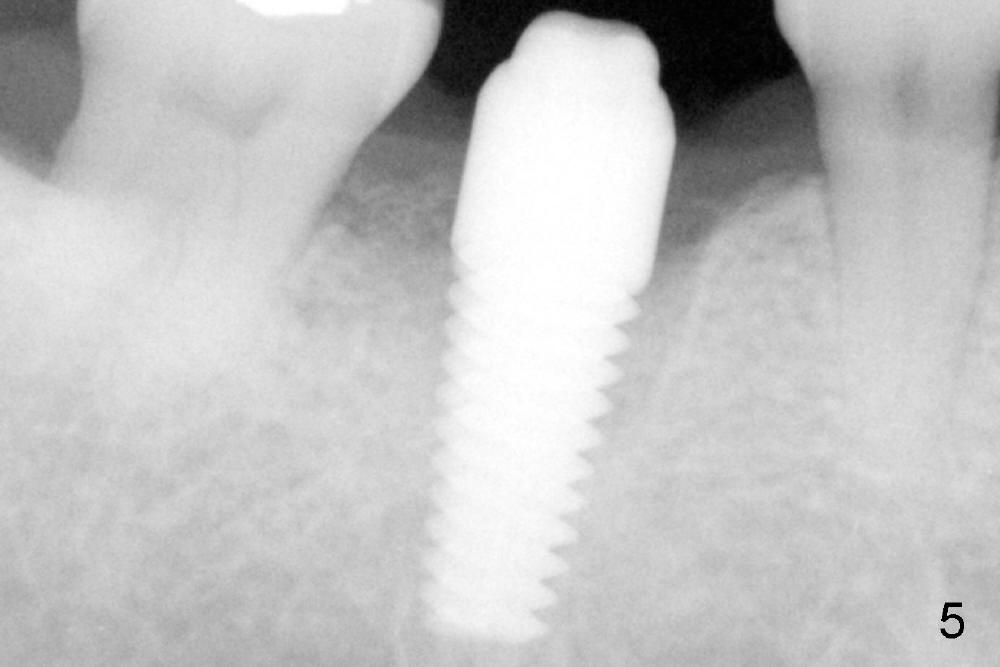

A gingiva-level implant (Fig.1 I) is placed immediately in the extraction site of the tooth #30 (*: remaining mesial and distal sockets after implantation). There appears to be no bone growth in the sockets 4 month postop (Fig.2), although the implant is stable. Clinically there is sign of infection (Fig.3 <) distobuccal to the implant (I). Since the patient is asymptomatic, it feels that the infection may resolve by itself. The abutment (A) is placed and impression is taken. Fourteen days later, the infection remains (Fig.4) after seating the permanent crown.

The infection may be related to chronic infection at the tooth #9. The latter is extracted, but the infection at the site of #30 does not resolve (Fig.5,6). The buccal flap is raised to reveal granulation tissue distobuccal to the implant (Fig.7). Bony defect and implant thread exposure are shown after debridement (Fig.8). Irradiated cancellous bone graft is placed to the defect (Fig. 9, Rocky Mountain Tissue Bank). The flap is closed with relative tension free. The definitive crown is temporarily cemented. The graft is exposed with no infection 2 week post grafting (Fig.10). The distobuccal defect appears to have healed 5 months post grafting (Fig.11) and the crown is permanently cemented (Fig.12). There is no buccal bone resorption, probably associated with immediate implantation. The patient remains asymptomatic 13 months postop.